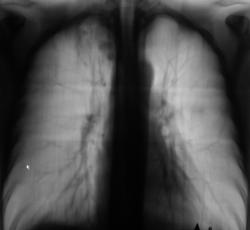

После расшифровки цифровых флюорограмм пациент "взят на контроль".

Флюорограмма и её фрагменты с увеличением.

Произведена рентгенография и томография - срезы стандартные.